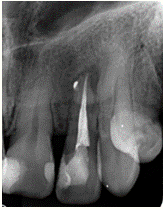

Figura 3: Control radiográfico después de 8 meses en donde se observa reparo óseo a nivel apical y recuperación de la cresta ósea. Fecha: 26/04/2023

Fuente: Dra. Karina Tito, 2023